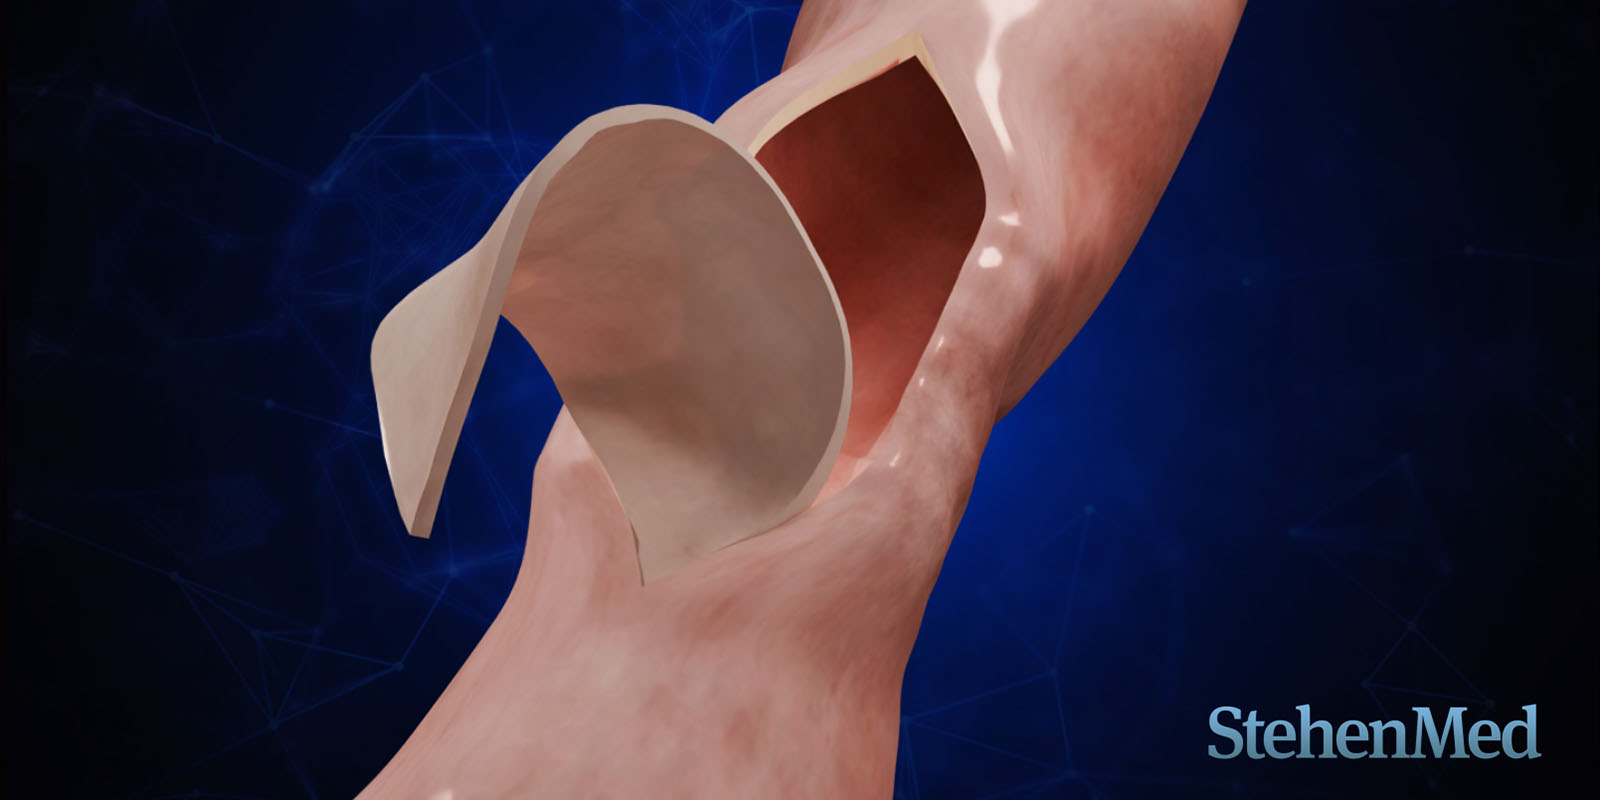

Visualización del procedimiento para el tratamiento de la estrechez de ureta peneana.

Categoría: Animación 3D - Procedimiento

Conceptos clave: Injerto, Estrechez, Uretra

Duración: 1m 51s